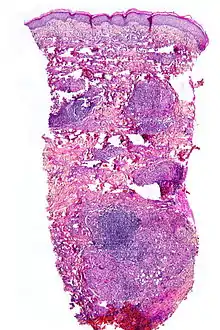

The exact cause of this condition is not known, but it involves collagen degeneration and a granulomatous response in the layer of the skin called the dermis, often affecting the deeper fat layer and thickening dermal blood vessels.

Although the exact cause of this condition is not known, it is an inflammatory disorder characterised by collagen degeneration, combined with a granulomatous response. It always involves the dermis diffusely, and sometimes also involves the deeper fat layer. Commonly, dermal blood vessels are thickened (microangiopathy).[3]

NL is diagnosed by a skin biopsy, demonstrating superficial and deep perivascular and interstitial mixed inflammatory cell infiltrate (including lymphocytes, plasma cells, mononucleated and multinucleated histiocytes, and eosinophils) in the dermis and subcutis, as well as necrotising vasculitis with adjacent necrobiosis and necrosis of adnexal structures. Areas of necrobiosis are often more extensive and less well defined than in granuloma annulare. Presence of lipid in necrobiotic areas may be demonstrated by Sudan stains. Cholesterol clefts, fibrin, and mucin may also be present in areas of necrobiosis. Depending on the severity of the necrobiosis, certain cell types may be more predominant. When a lesion is in its early stages, neutrophils may be present, whereas in later stages of development lymphocytes and histiocytes may be more predominant.